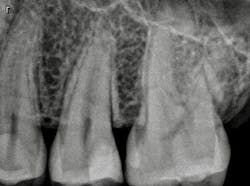

When a carious lesion and the Class II cavity preparation extend near to or apical to the cementoenamel junction, the sandwich technique can be used. The technique is described as a layering of various restorative materials within the cavity preparation. It involves placing RMGI at the base of the cavity preparation, followed by curing and the addition of composite restoratives to complete the restoration. If the remaining layers of composite resin completely encase the RMGI, it is considered a "closed" sandwich technique. If the RMGI is exposed to the oral environment at the base of the restoration, it is considered an "open" sandwich technique (figures 1a and 1b).

Figures 1a and 1b: RMGI sandwich techniques

This technique is not new and was originally proposed by Suzuki and Jordan. (4) According to Liebenberg, "The open-sandwich technique allows the least amount of microleakage of the various direct restorative options currently available." (5,6) This occurs because traditional composite bonding at the cavosurface and interproximal sites often have a complex combination of substrates that include enamel and varying levels of dentin, depending on the depth of the lesion. Liebenberg continues, "For dentin bonding, it appears far easier to achieve a seal than to maintain it, and in vivo studies have confirmed that resin-dentin bonds degrade in the oral cavity." (5,7)